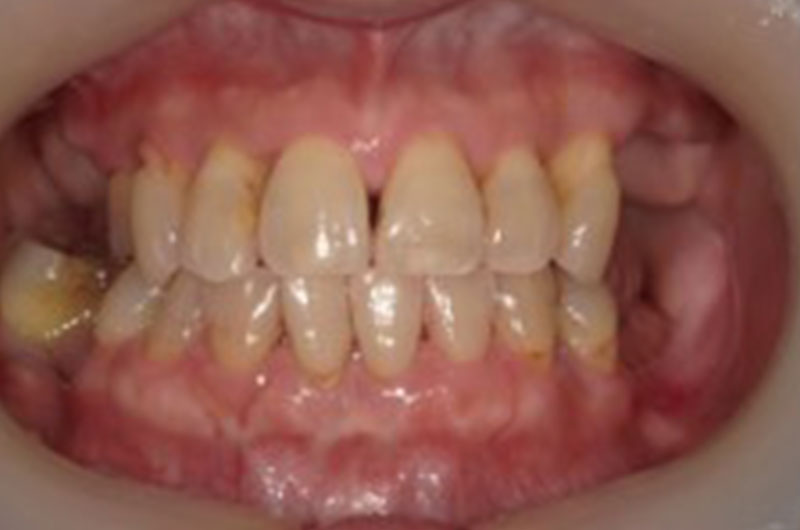

case13

症例13

歯の表面の赤と青の着色は咬み合せ確認の為の一時的なものです。

| 治療ケース | 骨造成(GBR)、インプラント埋入、オールセラミッククラウン |

| 治療結果 | 歯のない所を治療したいとの主訴で来院されました。虫歯や破折で抜歯が必要な状態でした。抜歯、骨造成(GBR)を行い待機期間を経て1次手術、2次手術を行いプロビジョナルを装着後問題の無いことを確認して最終上部構造を装着。歯が入った後経過も良く、安定している状態です。 |

| 治療開始月 | 2020年10月 |

| 治療期間 | 約7ヶ月 |